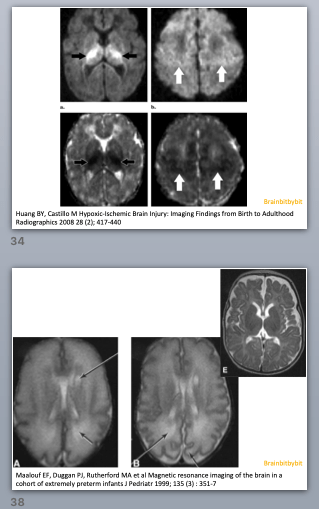

At birth the brain is largely unmyelinated. In the supratentorial brain of neonates myelinated white matter is seen only in the corticospinal tracts. In the first years of life the other axons become myelinated. The sequence of myelination is intuitive: After the corticospinal tract, the central structures including the internal capsule and corpus callosum myelinate. Then parietal (sensory), occipital (visual) and temporal lobe, and finally the frontal lobe (everybody thinks babies are cute anyway).

In the first 6 months the T1 weighted image is most useful to look at myelination. Myelin is fatty and proteinacous with high T1 signal, the extracellular space between the layers of myelin around the axons is aqueous. When the child gets older the water content and T2 hyper intensity decreases and after 6 -12 months the T2 weighted image is best to assess myelination. Visually at 24 months myelination should have an adult pattern on the T1 weighted images and an almost adult pattern with only hyperintensity in the terminal zones on the T2 weighted images. However, myelination is not finished at the age of 2 years: when quantifying the T1 relaxation time, progressive shortening is measured until adulthood indicating that myelination is an ongoing process.